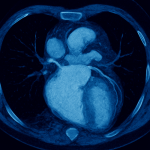

Aktuelles und Wissenswertes

zu Herz-Kreislaufkrankheiten

Aktuelles und Wissenswertes zu Herz-Kreislaufkrankheiten